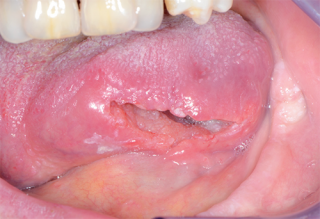

Questa crescita può inizialmente essere molto piccola e poco evidente, ma con il tempo può espandersi e coinvolgere i tessuti circostanti. Le aree più frequentemente interessate sono la lingua, il pavimento della bocca e le gengive, anche se nessuna zona è completamente esclusa.

Col passare del tempo, queste cellule alterate possono diventare sempre più numerose e formare una lesione visibile. In una fase iniziale può trattarsi di una macchia o di una piccola ulcera che non guarisce. Se non individuata e trattata, la situazione può evolvere verso una forma più seria.

Uno degli aspetti più importanti riguarda la capacità di riconoscere i segnali precoci. I tumori del cavo orale, nelle fasi iniziali, possono manifestarsi con sintomi apparentemente innocui.

Una piaga che non guarisce, una macchia bianca o rossa, un ispessimento della mucosa o una sensazione persistente di dolore possono essere segnali da osservare con attenzione. Anche difficoltà nella masticazione o nel parlare meritano un approfondimento, soprattutto se persistono nel tempo. Intervenire precocemente aumenta in modo significativo le possibilità di trattamento efficace.